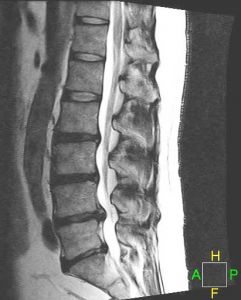

DIAGNOSIS

A herniated disc may be diagnosed after a complete history and comprehensive physical exam. In addition, several diagnostic tests can be used. Imaging studies at the Virginia Spine Institute are usually a first step in understanding spine pathology. These include standing and bending X-rays to evaluate spinal alignment, stability and disc space height. Your doctor will determine whether additional tests are needed. An MRI is the standard imaging to assess disc and nerve pathology. An EMG may be used to determine which specific nerves are involved and the extent of possible nerve damage.

LUMBAR DISC HERNIATIONS ON MRI